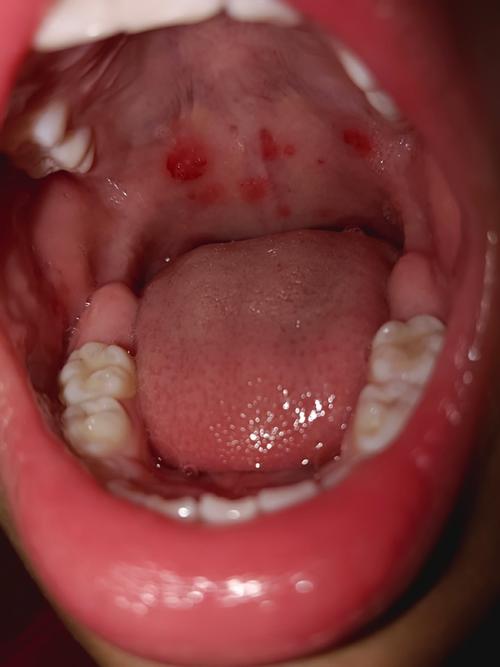

- 口腔水泡/溃疡: 在喉咙、舌、颊粘膜、上颚等处出现小水泡,水泡破溃后形成溃疡,孩子会非常疼痛,导致流口水、拒食、哭闹。

- 口腔水泡/溃疡: 症状非常明显,集中在咽峡部,即扁桃体、软腭、悬雍垂(小舌头)等后咽部位置,溃疡会引起剧烈的咽痛。